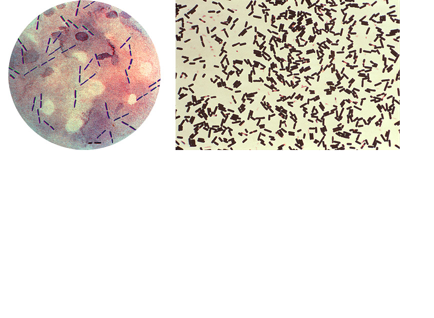

Botulism

Clostridium Perfringens